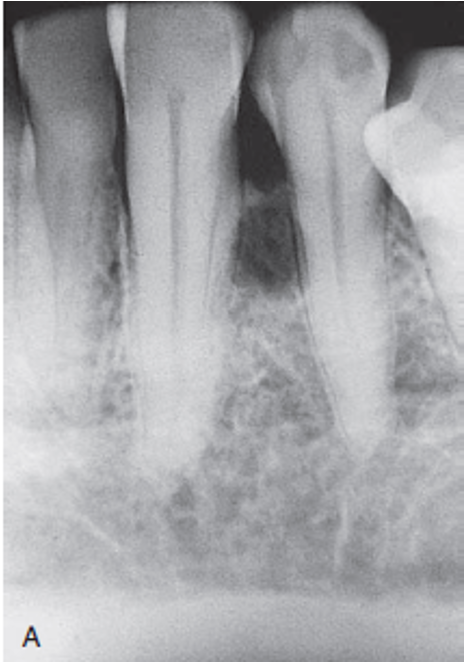

The most common cyst observed in the oral cavity is caused by pulpal inflammation and is called a(n) _____ cyst.

a. dentigerous

b. eruption

c. radicular

d. primordial

The radicular cyst is the most common cyst observed in the oral cavity. It is caused by pulpal inflammation. A dentigerous cyst forms around the crown of an unerupted or developing tooth. An eruption cyst is found in the soft tissue around the crown of an erupting tooth. A primordial cyst develops in place of a tooth, usually the third molar or posterior to an erupted third molar.